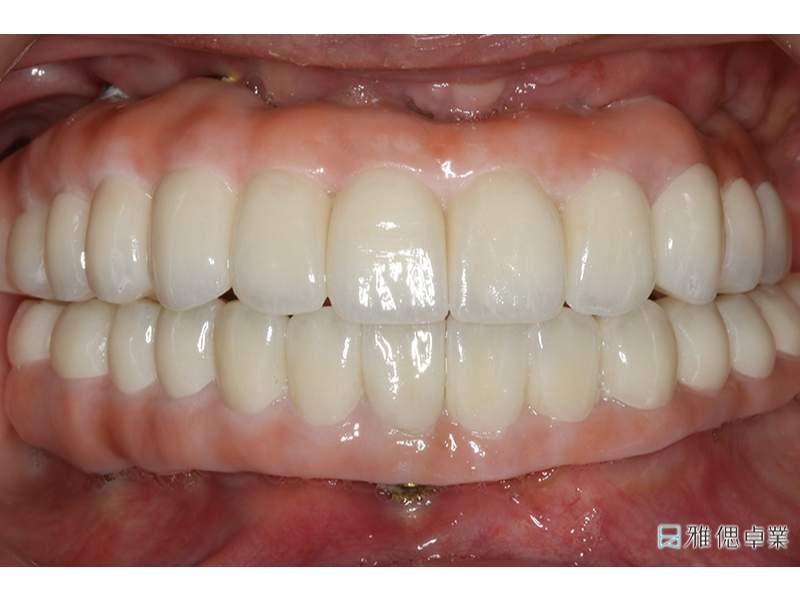

術後

All-On-6全口重建的最大好處在於可以短時間完成手術,與傳統植牙相比之下,能使用更短的時間恢復笑容,以及享受食物,經過All-On-6全口重建治療後,徹底改善了原本活動假牙遇到的問題,不需要再使用假牙黏著劑也不用擔心鬆動的問題,飲食上也恢復正常,不用擔心咬不動的問題。個案說,又能用牙齒咀嚼食物的感覺真的很好。完成療程的朋友們,都非常滿意All-On-6全口重建為生活帶來的改變。

All-On-6一日重建術後的生活,個案可以盡情展現自信笑容,輕鬆享受美食,不再有咀嚼困難。鄭醫師表示「讓醫師能夠繼續努力不懈的動力,相信就是看見患者有好的改變,並同時謹守幫助患者想要變得更好、更有自信的初衷。」